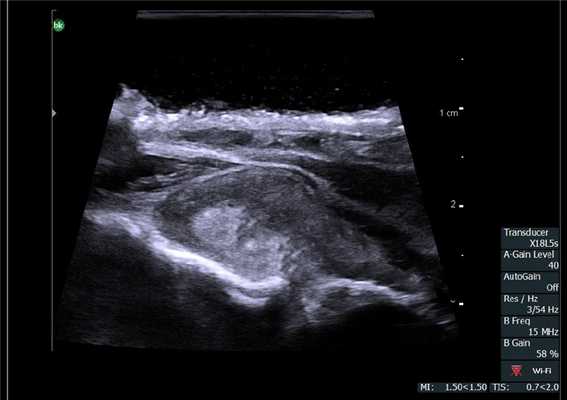

Важным моментом является интраоперационный осмотр зон лимфоотока. Лимфатические узлы брюшной полости могут претерпеть изменения как при воспалительных заболеваниях, так и при метастатическом поражении [27,28]. Интраоперационное исследование лимфатических узлов с целью дифференциальной диагностики изменений в узлах проводят во всех областях хирургии [29]. ИОУЗИ позволяет с высокой достоверностью говорить о наличие лимфаденопатии, однако четко определить характер поражения по данным ультразвукового исследования не всегда возможно.

Лимфатические узлы. Сканирование интраоперационным датчиком 8815